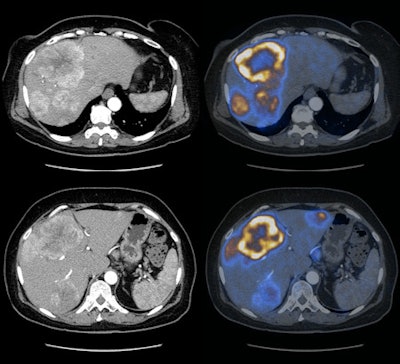

| Contrast-enhanced CT (left) of a solid papillary neuroendocrine carcinoma with corresponding liver metastases, compared to the same region with DOPA-enhanced PET/CT (right). Images courtesy of Dr. Patrick Veit-Haibach. |

With the additional information provide by DOPA-PET/CT, which included resection of primary tumors, metastases, and newly found lesions, therapy changed in 17 (26%) of the 65 cases from surgery to chemotherapy. In three cases, planned therapy was spared.